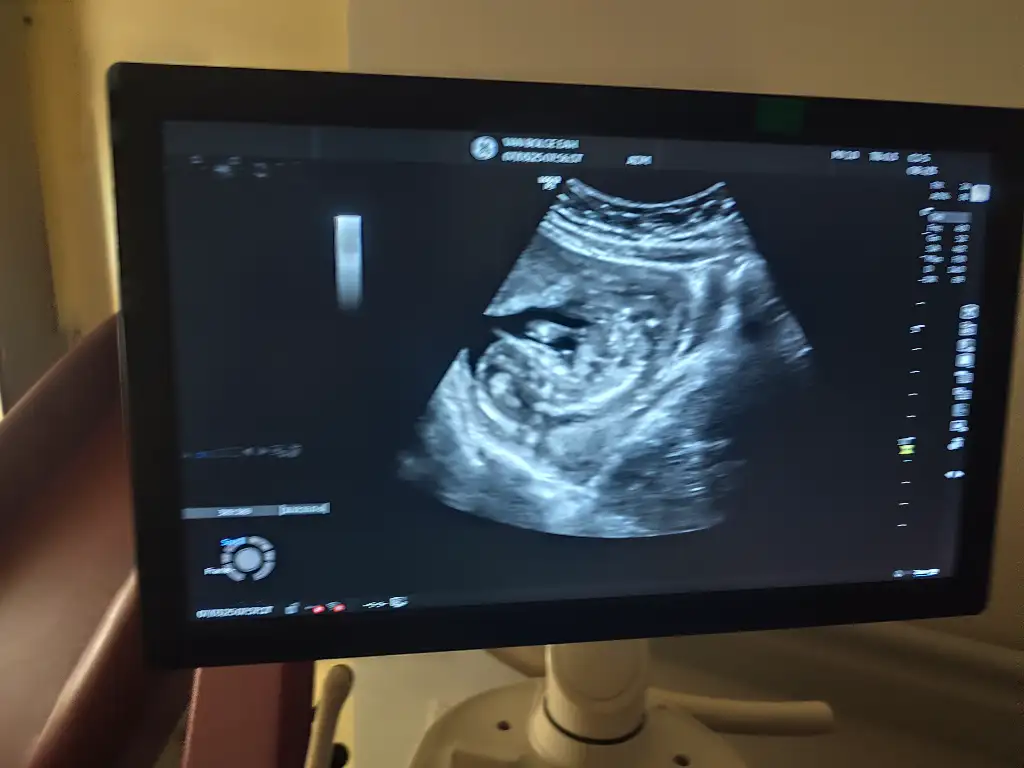

Benimkine de bakarmısnız 8 hafta 6 günlük karımdan ulturason görüntüsüVajinal bakıldı demişsiniz, kız olabileceğini düşünüyorum Ramzi teorisine göre.

Çok küçük daha tabi 7-8 haftalık olsa daha iyi anlaşılırdı

Benimde ultrason fotoğrafinda keseye bakıp tahmin edebilirmsnzGörüntü çok net değil ama erkek olabilir